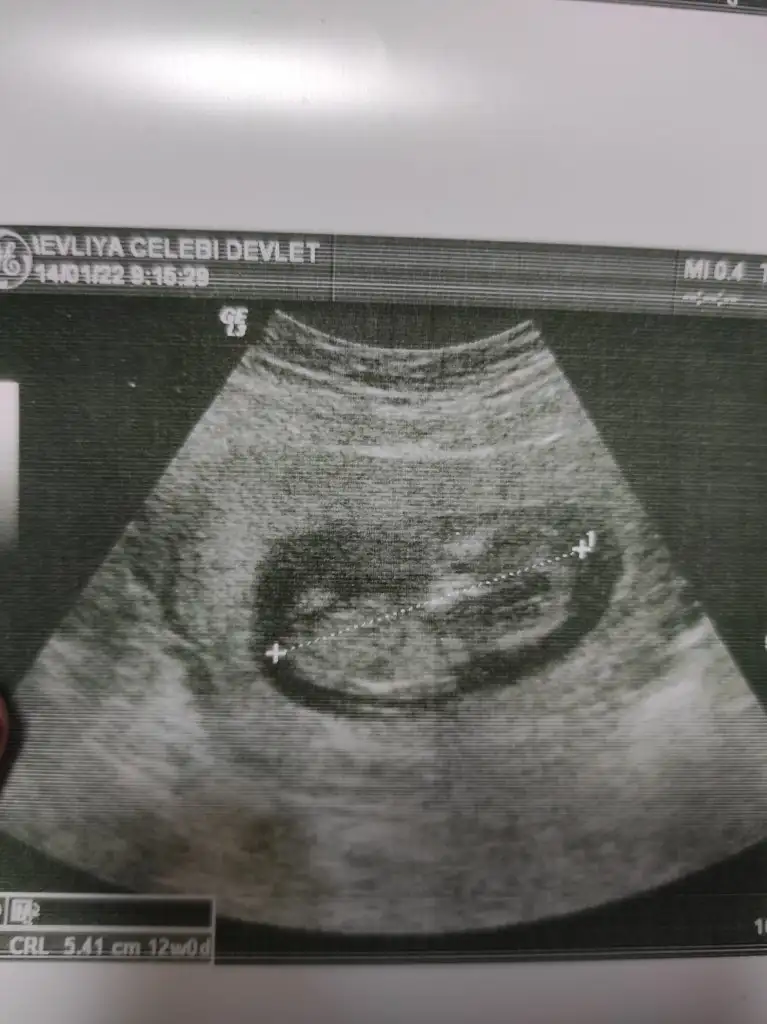

• IMG_20220114_092252.webp

IMG_20220114_092252.webp

39,4 KB · Görüntüleme: 62

• IMG_20220114_092247.webp

IMG_20220114_092247.webp

36,8 KB · Görüntüleme: 70